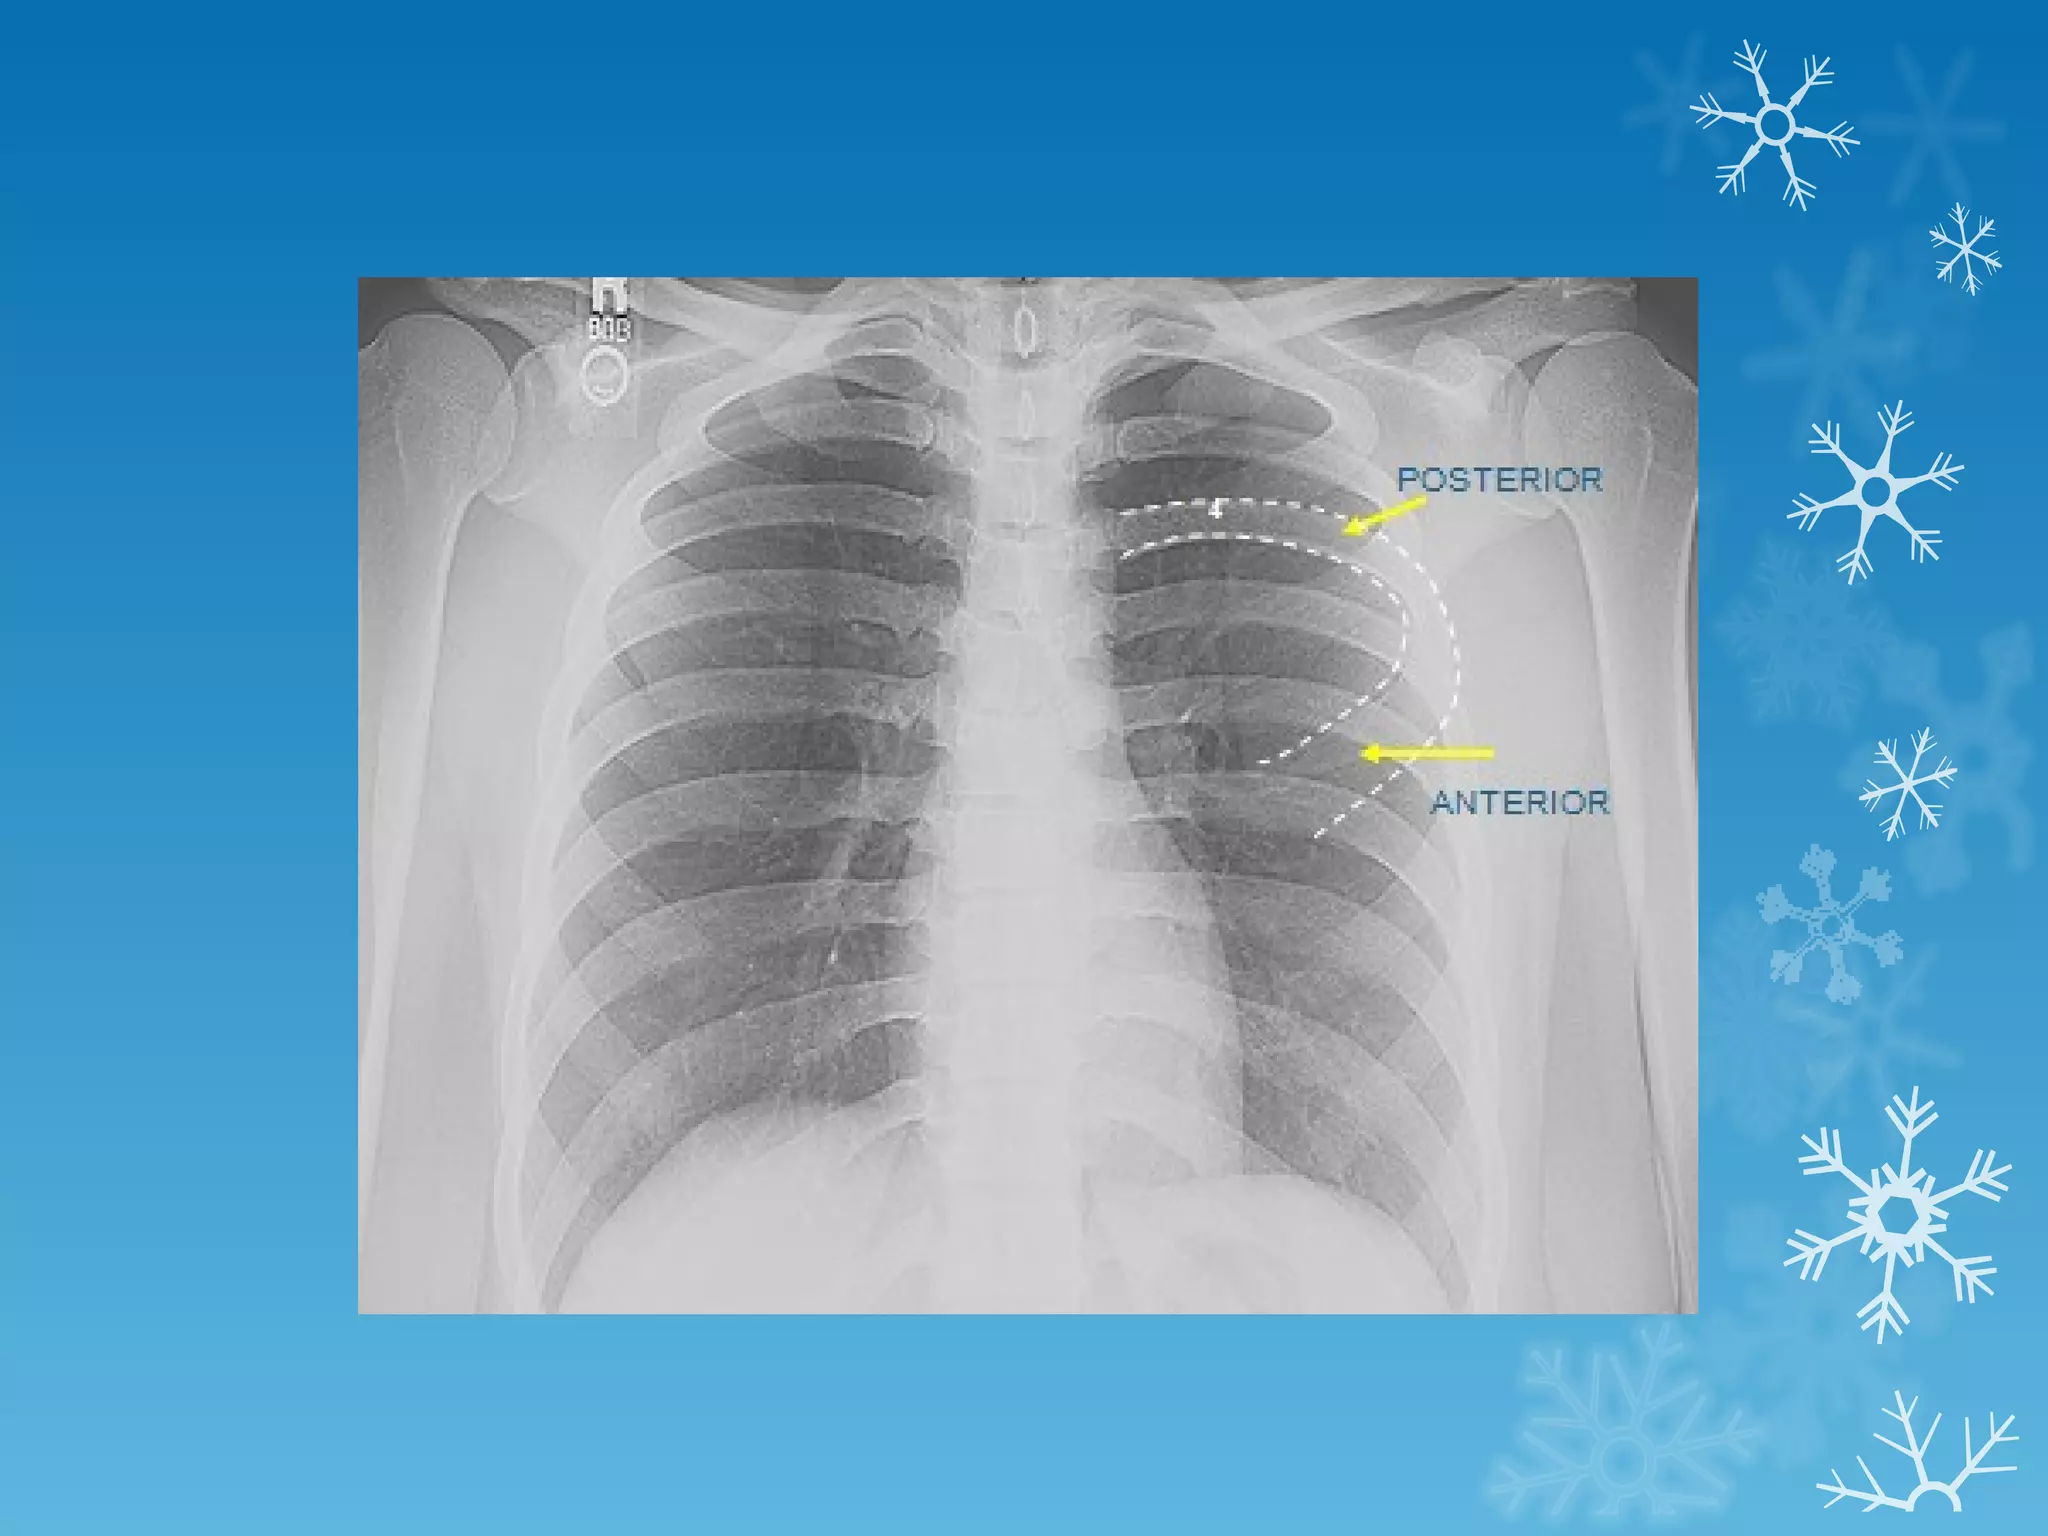

This document discusses chest x-ray interpretation and provides guidance on evaluating x-rays. It explains that tissue density determines how an x-ray beam penetrates, with denser tissues appearing whiter and less dense tissues appearing blacker. It also outlines different chest x-ray views and factors to consider like patient orientation, age, gender, and rotation. Abnormalities are described as appearing too white, too black, too large, or in the wrong place. The document stresses a systematic approach of identifying, localizing, describing lesions, and providing differential diagnoses.